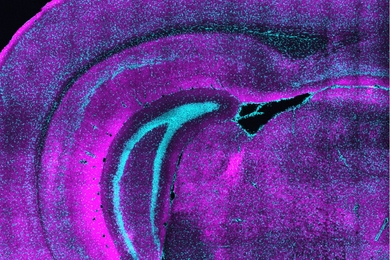

Impairments of this circuit may help to explain why some people with schizophrenia lose touch with reality.

By showing the problem derives from genetic mutations that lead to overexpression of a microRNA, MIT researchers’ study points to potential treatment.